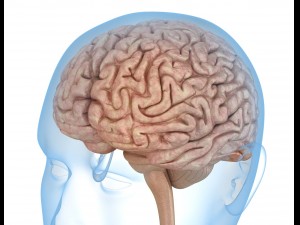

Brain with meninges scalp detailed labelled 3D 3D मॉडल

A blend model of brain along with its covering layers (meninges), skull bone and scalp labelled in detail and anatomically precise. The parts depicted are white, gray, pia, arachnoid, dura, bone, skin, fat, aponeurosis, periosteum, falx cerebri and more.